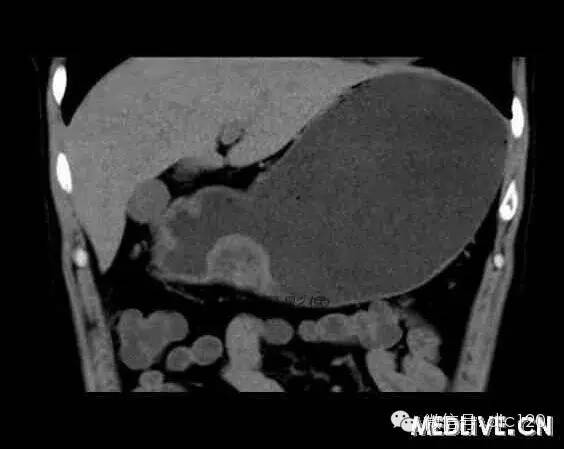

【病例】 胃異位胰腺

男,36歲,間斷性返酸噯氣3年,3個月前出現上腹疼痛,饑餓時加重。圖1-3為CT平掃,圖4-6分別為CT增強掃描的動脈期、門脈期和延遲期。影像表現 CT檢查可見胃幽門前區胃小彎側胃壁局限性增厚、隆起或伴凸向胃腔內的小結節灶,寬基地,境界光整,注射對比劑,增強掃描后,CT值可達50HU以上,與正常胰腺強化相仿。 確診依據 手術:異位于胃的胰腺 鑒別診斷 1、